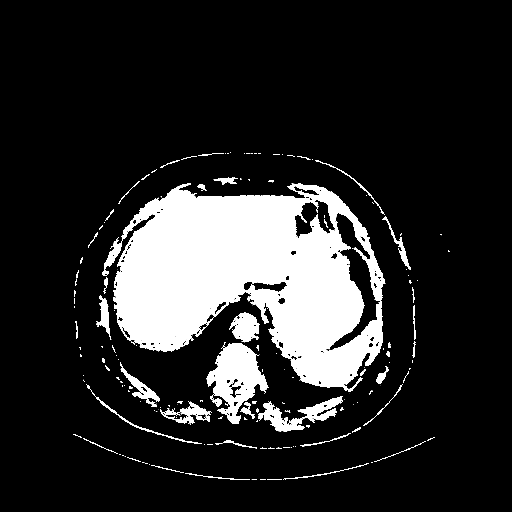

Original VENOUS CT scan

Full window (WL 1023.5, WW 4095 β†’ Low βˆ’1024, High +3071)

Actual HU range: [-1024.0, 3071.0]